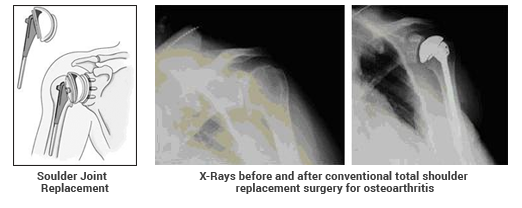

The surrounding muscles and tendons provide stability and support. Unfortunately, conditions like those listed above can lead to loss of the cartilage and mechanical deterioration of the shoulder joint. The result can be pain. You can have a stiff shoulder that grinds or clunks. This can lead to a loss of strength, decreased range of motion in the shoulder and impaired function. X-rays of the shoulder would show:

• Loss of the normal cartilage joint space

• Flattening or irregularity in the shape of the bone

• Bone spurs

• Loose pieces of bone and cartilage floating inside the joint

In severe cases, bone-on-bone arthritis may lead to erosion–wearing away of the bone.

The usual total shoulder replacement involves replacing the arthritic joint surfaces with a highly polished metal ball attached to a stem, and a plastic socket.

Total shoulder replacement

When both ball and the cup are badly effected but the shoulder has good muscles all around than the choice of anatomical total shoulder replacement is appropriate.